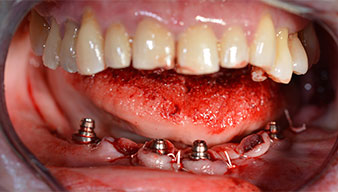

A three-dimensional cone beam computed tomography scan (CBCT, Planmeca) was performed to aid planning and minimize risks. This revealed that the quality and quantity of the available bone were sufficient for the surgery and immediate restoration using the Fast & Fixed method. Following the protocol for this concept, the implants are inserted at 35, 32, 42 and 45. Angling the distal implants by up to 45° shifts the emergence profile to posterior and generates a larger support polygon (Fig. 3).

Angled abutments (35°) were screwed in to compensate for the divergence of the distal implants, with the result that the emergence profile of all implants was as perpendicular as possible to the bite plane. This is a prerequisite for occlusal placement of the provisional and subsequently the permanent denture (Fig. 15 and 16).

The impression and bite registration were then performed so that the dental technician could begin producing the provisional restoration immediately. This was then screwed in on the same day (Fig. 17 and 18).